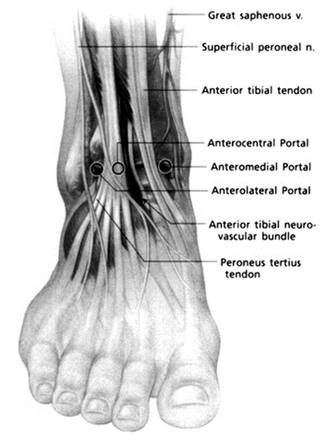

Describe ankle arthroscopy portals

Anteromedial

Anterolateral:

Anterocentral

Posterolateral

Posteromedial